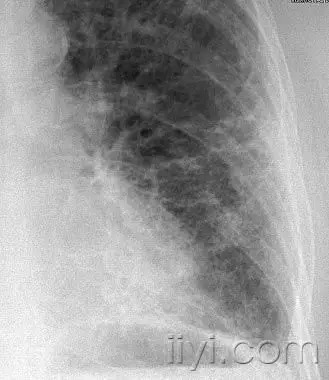

空气滞留(air trapping)

病生理:阻塞远端的气体滞留(通常是部分性)

CT:在呼气末CT上表现为实质密度升高程度低于正常肺实质,体积减小程度降低。当空气滞留较轻或者弥漫的时候,比较呼气末和吸气末CT是有帮助的。阻塞性血管病变造成的低灌注也表现低密度,有时候与本病鉴别比较困难。但是可以发现相关的气道病变,与血管性病变不同。